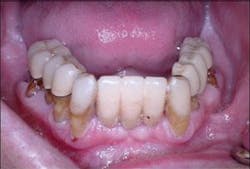

A healthy 55-year-old male presented for examination with a chief complaint being recurrent infection around multiple maxillary and mandibular teeth. Clinical examination revealed generalized severe periodontal disease with hopeless maxillary and mandibular teeth. These teeth were Class II mobile with areas of localized suppuration and failing existing prostheses (Figure 1).

Figure 1 - Pretreatment photograph of mandibular teeth